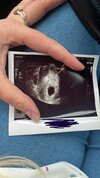

Cześć, znalazłam was wczoraj, czytałam do 4 rano i nieśmiało chciałabym dołączyć 😉 ciąża to wielka niespodzianka, zupełnie jej nie planowaliśmy, zawsze się zabezpieczaliśmy. Mam już 3 dzieci- najstarsza adoptowana córka 14 lat, później 7 latka i najmłodszy 3 latek. Synek urodził się niepełnosprawny, od kwietnia miałam maraton z lekarzami, wizytami, trochę chorób po drodze. Kompletnie nie pamiętam kiedy miałam ostatni okres, nie zwróciłam na to uwagi. W środę na USG 6+1, ale był widoczny tylko pęcherzyk ciążowy. Wg mojego lekarza ciąża jest młodsza o tydzień. Nie badałam bety, jestem na siebie zła, boję się że i tym razem coś będzie nie tak….najgorsze jest to, że 10 maja miałam rtg całego kręgosłupa, brałam silne leki :( ale już teraz nie mam na nic wpływu- czekam do kolejnej wizyty, która będzie 31 maja. Od kwietnia powiedziałam sobie dość i zabrałam się za swoje zdrowie- schudłam 7kg, poprawiłam wyniki- zmagam się z graves basedowa i insulinoopornoscią iiii jak już się cieszyłam, że super się czuję, to musiałam „zaskoczyć” 🫣 od kilku dni mdłości całą dobę, ból piersi, brzucha i okropne osłabienie….

Załączniki

• IMG_4665.jpeg